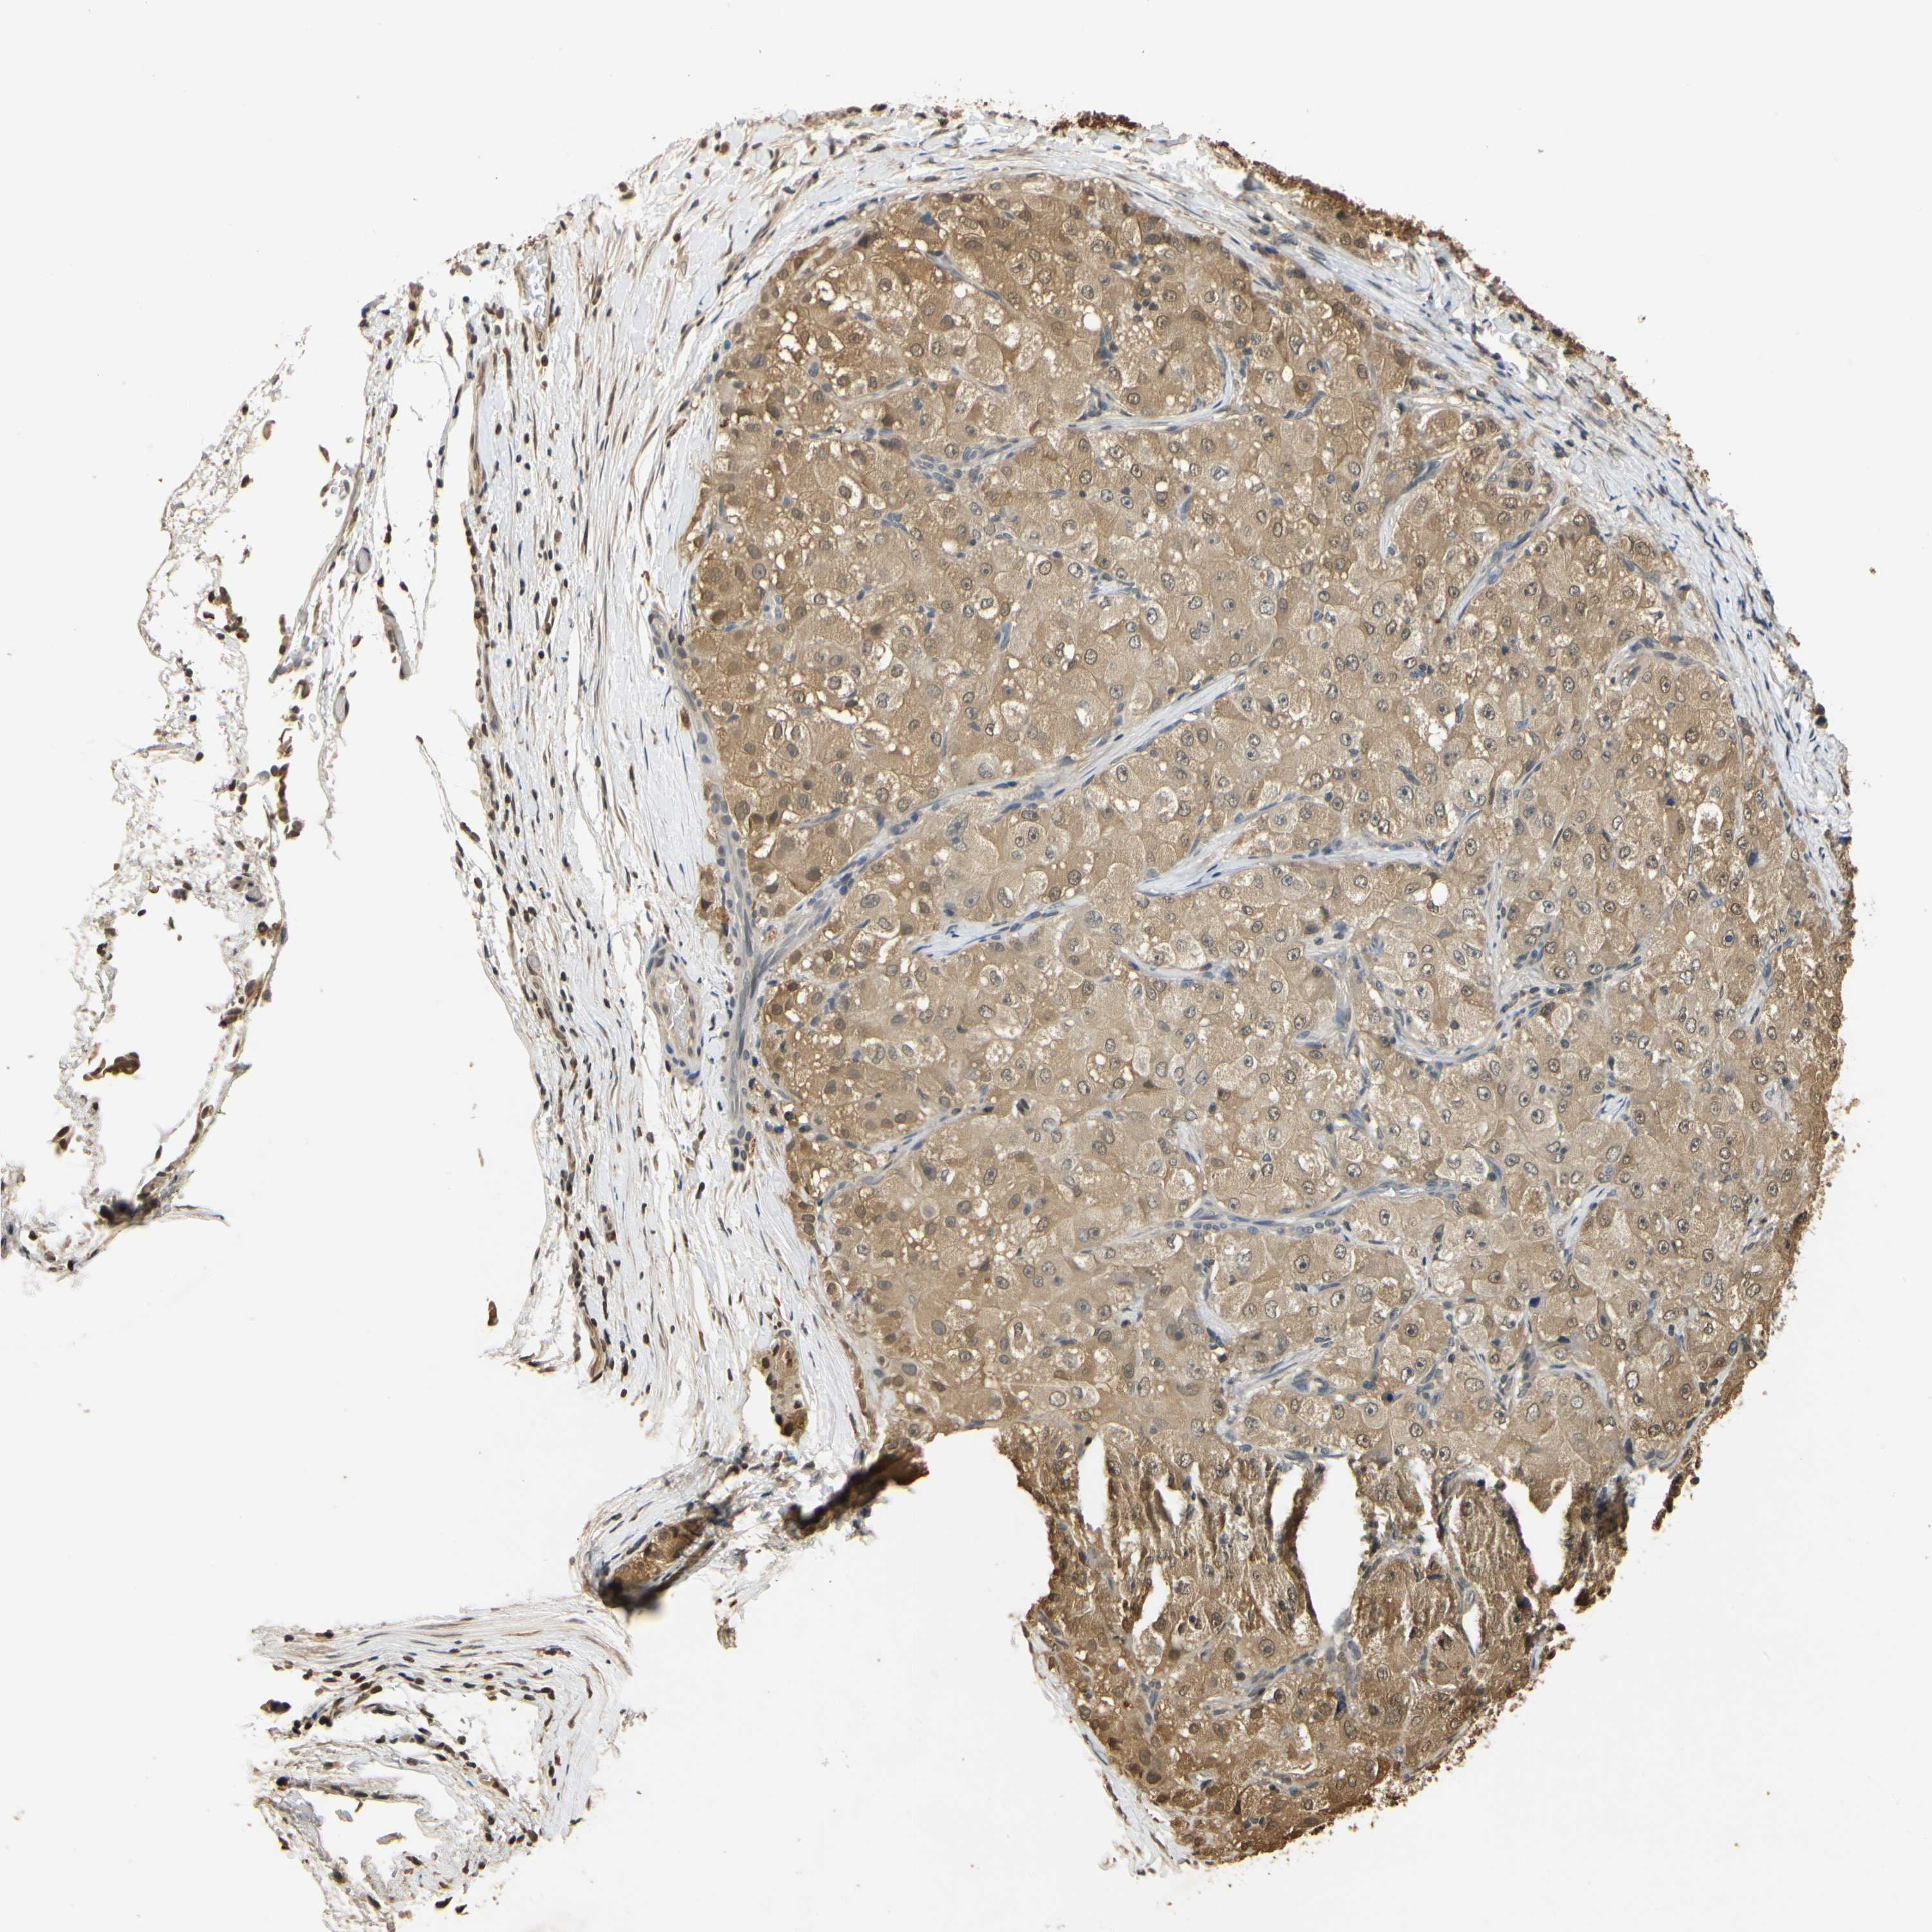

LIVER CANCER - Protein expressioni

A mouse-over function shows sample information and annotation data. Click on an image to view it in a full screen mode. Samples can be filtered based on level of antibody staining by selecting one or several of the following categories: high, medium, low and not detected. The assay and annotation is described here.

Note that samples used for immunohistochemistry by the Human Protein Atlas do not correspond to samples in the TCGA dataset.

Antibody stainingi

Antibody staining in the annotated cell types in the current human tissue is reported as not detected, low, medium, or high, based on conventional immunohistochemistry profiling in selected tissues. This score is based on the combination of the staining intensity and fraction of stained cells.

Each image is clickable and will lead to virtual microscopy that enables deeper exploration of all samples and also displays staining intensity scores, fraction scores and subcellular localization as well as patient and tissue information for each sample.

Antibody HPA001401

Antibody CAB008670

Staining

High

Medium

Low

Not detected

Intensity

Strong

Moderate

Weak

Negative

Quantity

>75%

75%-25%

<25%

None

Location

Nuclear

Cytoplasmic/membranous

Cytoplasmic/membranous,nuclear

Carcinoma, Hepatocellular, NOS

Cholangiocarcinoma